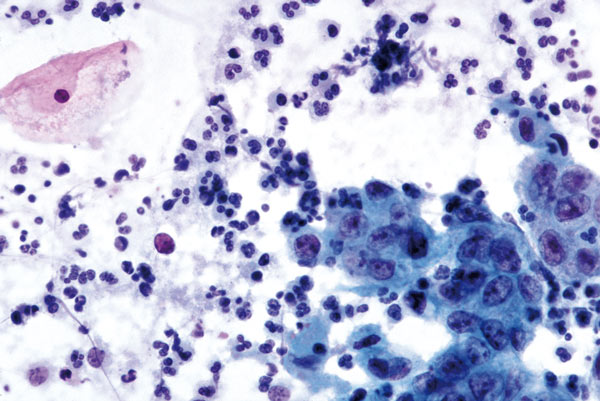

Mai

richtige Antwort:

d. Kleinzelliges Plattenepithelkarzinom (V-p)

- liegt in sehr lockeren Gruppen

- rundlich bis ovale, entrundete Zellkerne; in der Größe sind sie relativ gleichförmig

- stark vergröbertes Kernchromatin

- Tumordiathese